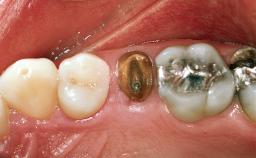

Replacement of a Maxillary Right Central Incisor Using an Early Loading Protocol

A healthy 26-year-old woman was referred for evaluation and treatment of her failing maxillary right central incisor (tooth 11). She reportedly traumatized the tooth at about age 9 and subsequently had repeated conventional and surgical endodontic procedures and fixed restorations. Despite these procedures, she had recurrent fistulas in the apical mucosa and a mid-facial pocket of 7 mm with suppuration. All other sites on the tooth probed 3 mm without inflammation. She presented with a medium biotype with triangularlyshaped teeth and a moderately high smile line, showing all of her papillas and a few millimeters of marginal gingiva in a full smile.Ceramic veneers were present on teeth 12, 21, and 22, and they were known to be somewhat bulky, eventually requiring replacement. She had a strong desire to avoid additional tooth preparation and would not consider a fixed dental prosthesis to replace tooth 11.